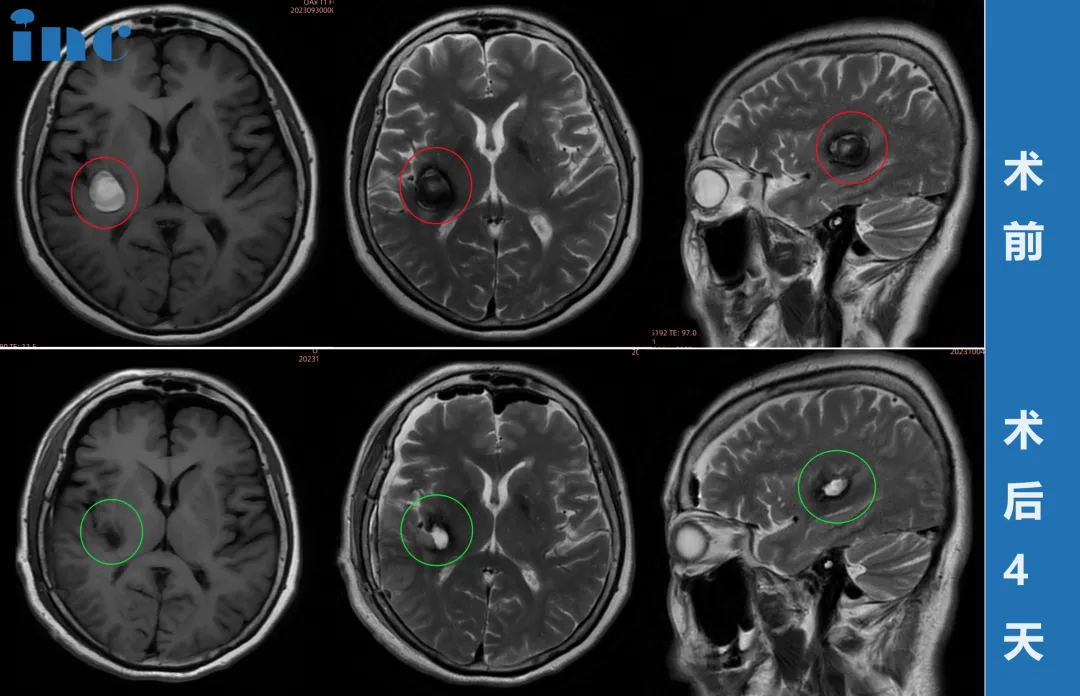

巴教授的這份責任與擔當打消了柯女士和家人所有顧慮。9月29日視頻咨詢,30日柯女士從東北飛赴蘇州,10月1日——國慶節(jié)當天,由巴教授主刀,國內神經外科團隊精密配合下,為她成功手術。術后核磁顯示,海綿狀血管瘤已完全切除,且沒有新的神經功能損傷。

基底節(jié)區(qū)海綿狀血管瘤影像